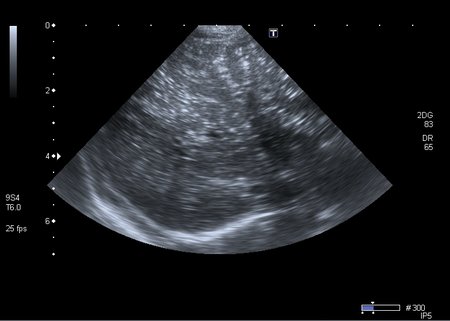

Хочу продолжить дискуссию, повод для этого - сегодняшний пациент 1 года 4 месяцев с клиникой кишечной инфекции и подозрением на инвагинацию. Инвагината не нашёл, но зато при УЗИ выявлены следующие изменения в печени

Кроме того был выражен феномен спонтанного контрастирования кровотока в портальной системе (пузырьки газа?). На рентгенограмме - единичные горизонтальные уровни в тонкой кишке, интерстициального пневматоза стенки газа в проекции портальной системы нет.

Хотелось бы узнать мнение общества о природе данного феномена.